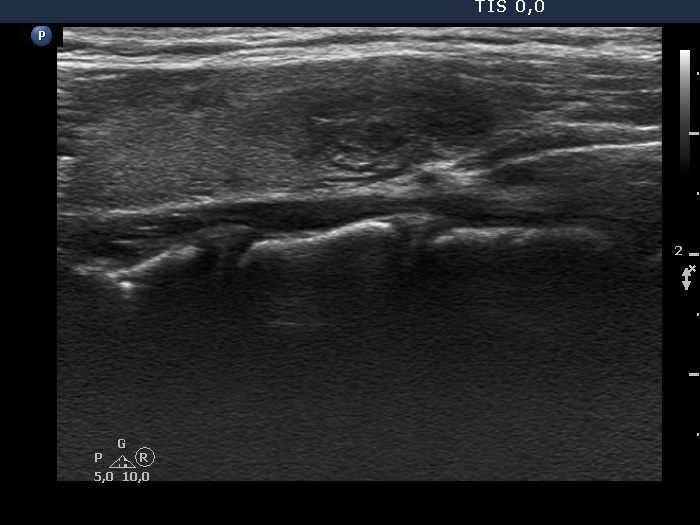

Halo sign and vascular pattern of nodules - case 2249

Follow-up investigation 3 years later (ultrasonographic picture 5)

Left lobe, longitudinal scan. The nodule does not have cystic areas.